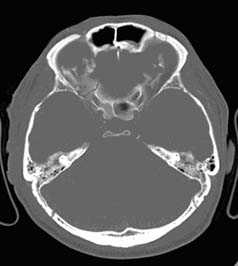

б - Изолированное кровоизлияние в ствол мозга (стрелка) у 12-летней девочки, ШКГ 3 балла. Примечание: травму ствола мозга лучше всего диагностировать с помощью МРТ. а - Кровоизлияние в таламус (стрелка) у молодого пациента, поступившего в глубокой коме (ШКГ 4 балла).

б - Пневмоцефалия у пожилого пациента с лобно-базальной травмой. а - Вклинение под серп мозга (одна стрелка), вызывающие гидроцефальное расширение контралатерального желудочка (двойная стрелка) из-за большой острой субдуральной гематомы.